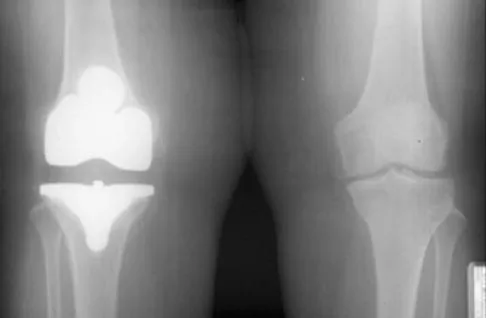

A 58-year-old man has anterior knee pain after undergoing total knee arthroplasty for osteoarthritis 2 years ago. He denies any history of trauma. A Merchant view is shown in Figure 20. What is the most likely cause of his pain?

Explanation

The patient has a patellar stress fracture after resurfacing in a total knee arthroplasty. Several studies have shown that over-resection of the patella to less than 12 to 15 mm increases anterior patellar surface strains to a point where the risk of fracture is increased. Increasing the patellar thickness, positioning of the femoral component, lateral releases, and component types have not been clearly associated with increased fracture risk. Reuben JD, McDonald CL, Woodard PL, Hennington LJ: Effect of patella thickness on patella strain following total knee arthroplasty. J Arthroplasty 1991;6:251-258. Hsu HC, Luo ZP, Rand JA, An KN: Influence of patellar thickness on patellar tracking and patellofemoral contact characteristics after total knee arthroplasty. J Arthroplasty 1996;11:69-80.